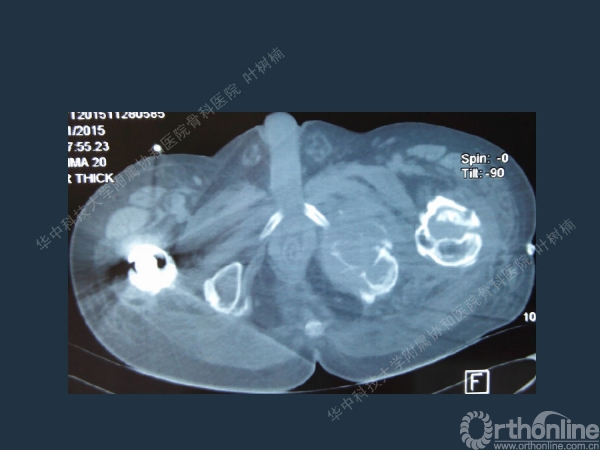

股骨侧翻修

髋臼缺损的处理